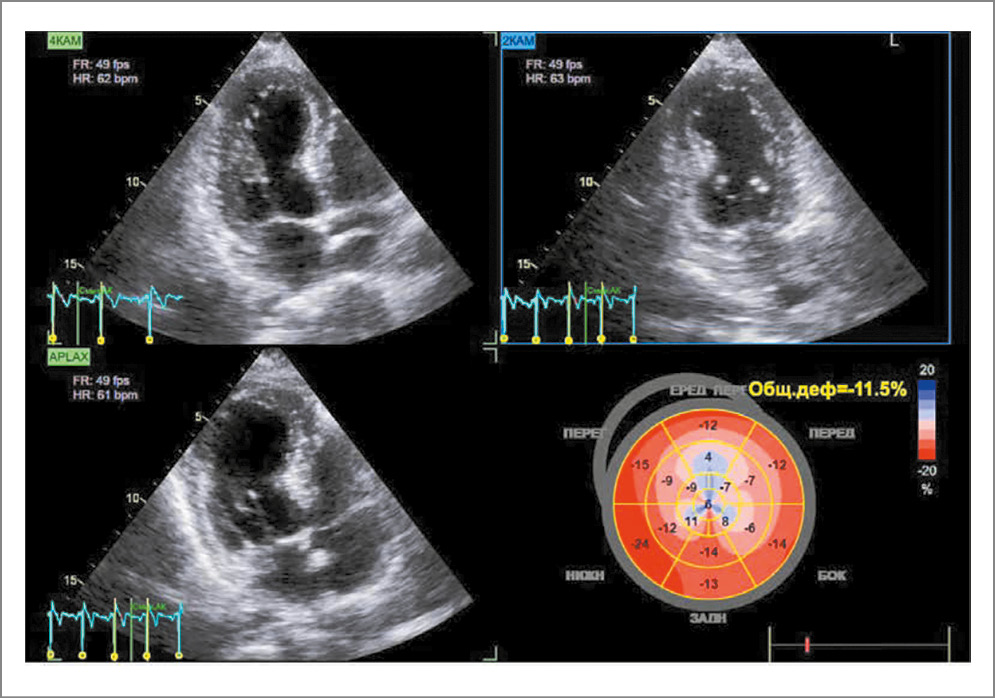

По результатам ЭхоКГ выявили снижение систолической функции в области верхушки и всех апикальных сегментов по типу дискинезии. Фракция выброса (ФВ) ЛЖ составила 46%, а глобальная продольная деформация (GLS) превышает -15%: GLS=-11,2% при норме менее -15%. Конечный диастолический размер ЛЖ – 4,49 см, конечный диастолический объем (КДО) ЛЖ – 101 мл, конечный систолический размер ЛЖ – 3,1 см, конечный систолический объем (КСО) ЛЖ – 51 мл, также определилась выраженная концентрическая гипертрофия миокарда ЛЖ (толщина межжелудочковой перегородки – 16 мм, толщина задней стенки ЛЖ – 13 мм, толщина верхушки и боковой стенки – 13 мм, индекс массы миокарда – 160 г/м2, масса миокарда – 261 г). Отмечены признаки нарушения диастолической функции ЛЖ по типу нарушения релаксации со снижением подвижности кольца митрального клапана (латеральный e’=0,03 м/с и перегородочный e’=0,04 м/с). Диастолическая дисфункция 1-го типа. Соотношение скорости пиков раннего и позднего наполнения ЛЖ (Е/А) равно 0,4 (рис. 2).

Рис. 2. Эхокардиограмма при поступлении в стационар.